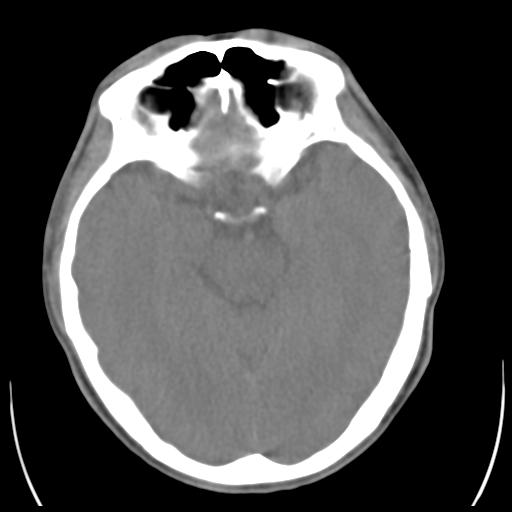

35m 鼻子时不时流血,头及右侧面部痛,颈部淋巴结未见明显大

软组织窗

考虑鼻咽癌侵犯颅底并突入右侧鼻腔;双侧中耳乳突炎。

蝶窦,后组筛窦及鼻咽部团块状软组织影,骨壁破坏,病变较广泛。考虑恶性肉芽肿。建议活检。

颅底骨质明显破坏 支持鼻咽癌 但病灶的边缘毛糙 不能除外炎性

蝶窦,后组筛窦及鼻咽部团块状软组织影,骨壁破坏,病变较广泛。考虑炎性肉芽肿性病变可能。建议活检。